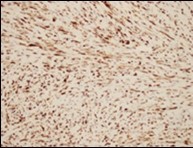

The neoplasm frequently infiltrates abutting skeletal muscle. Occasionally, tumefaction denominates hyper-cellular foci, tumour necrosis, cellular or nuclear atypia and mitotic figures, features which are characteristic of intermediate to high grade sarcoma. Localized tumour reoccurrence may be hyper-cellular with enhanced mitotic activity 4, 5. On ultrastructural examination, fibroblastic differentiation is exemplified 5. Figure 1, Figure 2, Figure 3, Figure 4, Figure 5, Figure 6, Figure 7, Figure 8.

Figure 6.Low grade fibromyxoid sarcoma immune reactive to MUC4(14).

Assessment of precise immune reactivity is beneficial although staining profile of the benign neoplasm appears nonspecific.

High molecular weight glycoprotein, mucin 4(MUC4) is a sensitive, specific, contemporary immune marker to ascertain and distinguish low grade fibromyxoid sarcoma from histologically identical neoplasms.

A comprehensive (100%), intense, diffuse cytoplasmic immune staining is discerned with MUC4. Gene expression profiling can also be adopted to enunciate MUC4.

Spindle cell neoplasms such as desmoid tumour or soft tissue perineurioma mandating distinction from low grade fibromyxoid sarcoma are immune non reactive to MUC46, 7.